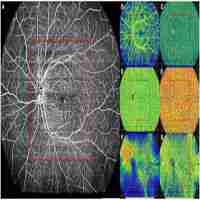

| Abstract | Background To investigate alterations in retinal microvasculature in eyes with preclinical diabetic retinopathy (DR) using ultra-wide field swept-source optical coherence tomography angiography (UWF SS OCTA). Methods Prospective cross-sectional study. Fifty-five eyes of 30 diabetic patients without clinical retinal signs were included. All subjects underwent OCTA examination with a 12 × 12 mm2 field of view of 5 visual fixations (1 central fixation and 4 peripheral fixations) to compose a UWF OCTA image. In the UWF images, the central area corresponded to the original central image obtained using central fixation, and the peripheral area was the remaining area. Lesions, including nonperfusion areas (NPAs), microvascular dilation and tortuosity, and neovascularization (NV), were recorded in different areas. Diabetes history was also recorded. Results Peripheral areas presented significantly more microvascular dilation and tortuosity than central areas (P = 0.024) and more NPAs than central areas, with borderline significance (P = 0.085). The number of lesion types was associated with HbA1c levels in the peripheral and overall areas (all P values < 0.001). Conclusions UWF SS OCTA is a promising imaging method for detecting vascular alterations in diabetic eyes without clinical signs to reveal retinal microvascular alterations. These alterations were correlated with systemic conditions. |